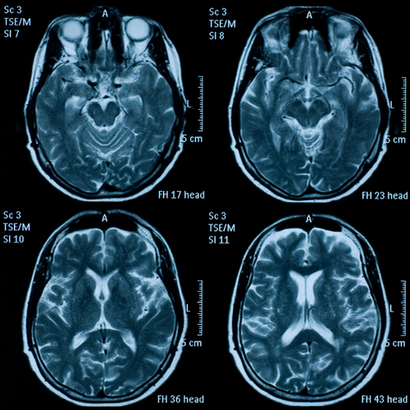

I soggetti sono stati sottoposti a risonanza magnetica cranica, all’inizio e dopo due anni dal trattamento. Queste analisi insieme a quelle del plasma hanno dimostrato che nei soggetti con elevata concentrazione di acidi grassi, il trattamento con le vitamine aveva rallentato il tasso di crescita di atrofia del 40,0% rispetto al placebo.